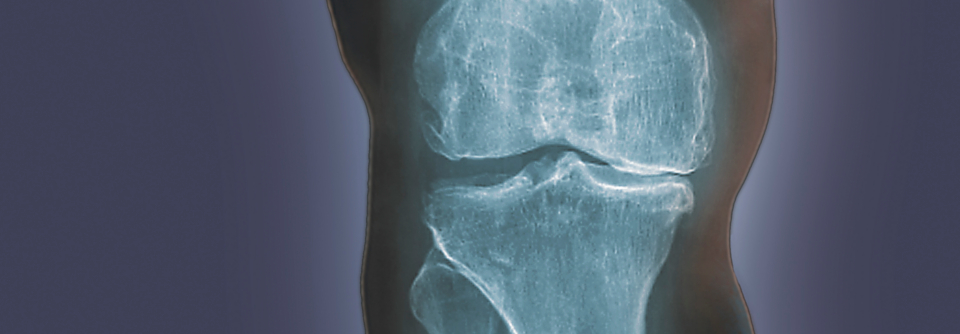

Personen mit Knieschmerzen ohne Arthrose beschreiben ihre Beschwerden dagegen eher als pieksend. Personen mit Knieschmerzen ohne Arthrose beschreiben ihre Beschwerden dagegen eher als pieksend. © Dragana Gordic – stock.adobe.com

Ob Knieschmerzen einem (beginnenden) Gelenkverschleiß geschuldet sind oder nicht, lässt sich u. a. anhand der Schmerzcharakteristik abschätzen.

Personen mit Knieschmerzen ohne Arthrose beschreiben ihre Beschwerden dagegen eher als pieksend. Dies ergibt sich aus einer Studie mit 94 Patientinnen und Patienten, die unter Knieschmerzen litten. Bei 49 von ihnen lag eine Arthrose vor. Sie waren im Schnitt 21 Jahre älter als die Studienteilnehmenden ohne Gonarthrose.